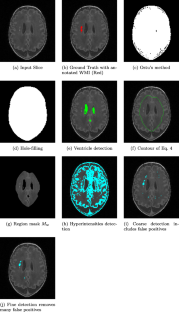

White matter injury (WMI) is the most prevalent brain injury in the preterm neonate leading to developmental deficits. However, detecting WMI in magnetic resonance (MR) images of preterm neonate brains using traditional WM segmentation-based methods is difficult mainly due to lack of reliable preterm neonate brain atlases to guide segmentation. Hence, we propose a segmentation-free, fast, unsupervised, atlas-free WMI detection method. We detect the ventricles as blobs using a fast linear maximally stable extremal regions algorithm. A reference contour equidistant from the blobs and the brain-background boundary is used to identify tissue adjacent to the blobs. Assuming normal distribution of the gray-value intensity of this tissue, the outlier intensities in the entire brain region are identified as potential WMI candidates. Thereafter, false positives are discriminated using appropriate heuristics. Experiments using an expert-annotated dataset show that the proposed method runs 20 times faster than our earlier work which relied on time-consuming segmentation of the WM region, without compromising WMI detection accuracy.

Key Steps of Segmentation-free WMI Detection

Fig. 2